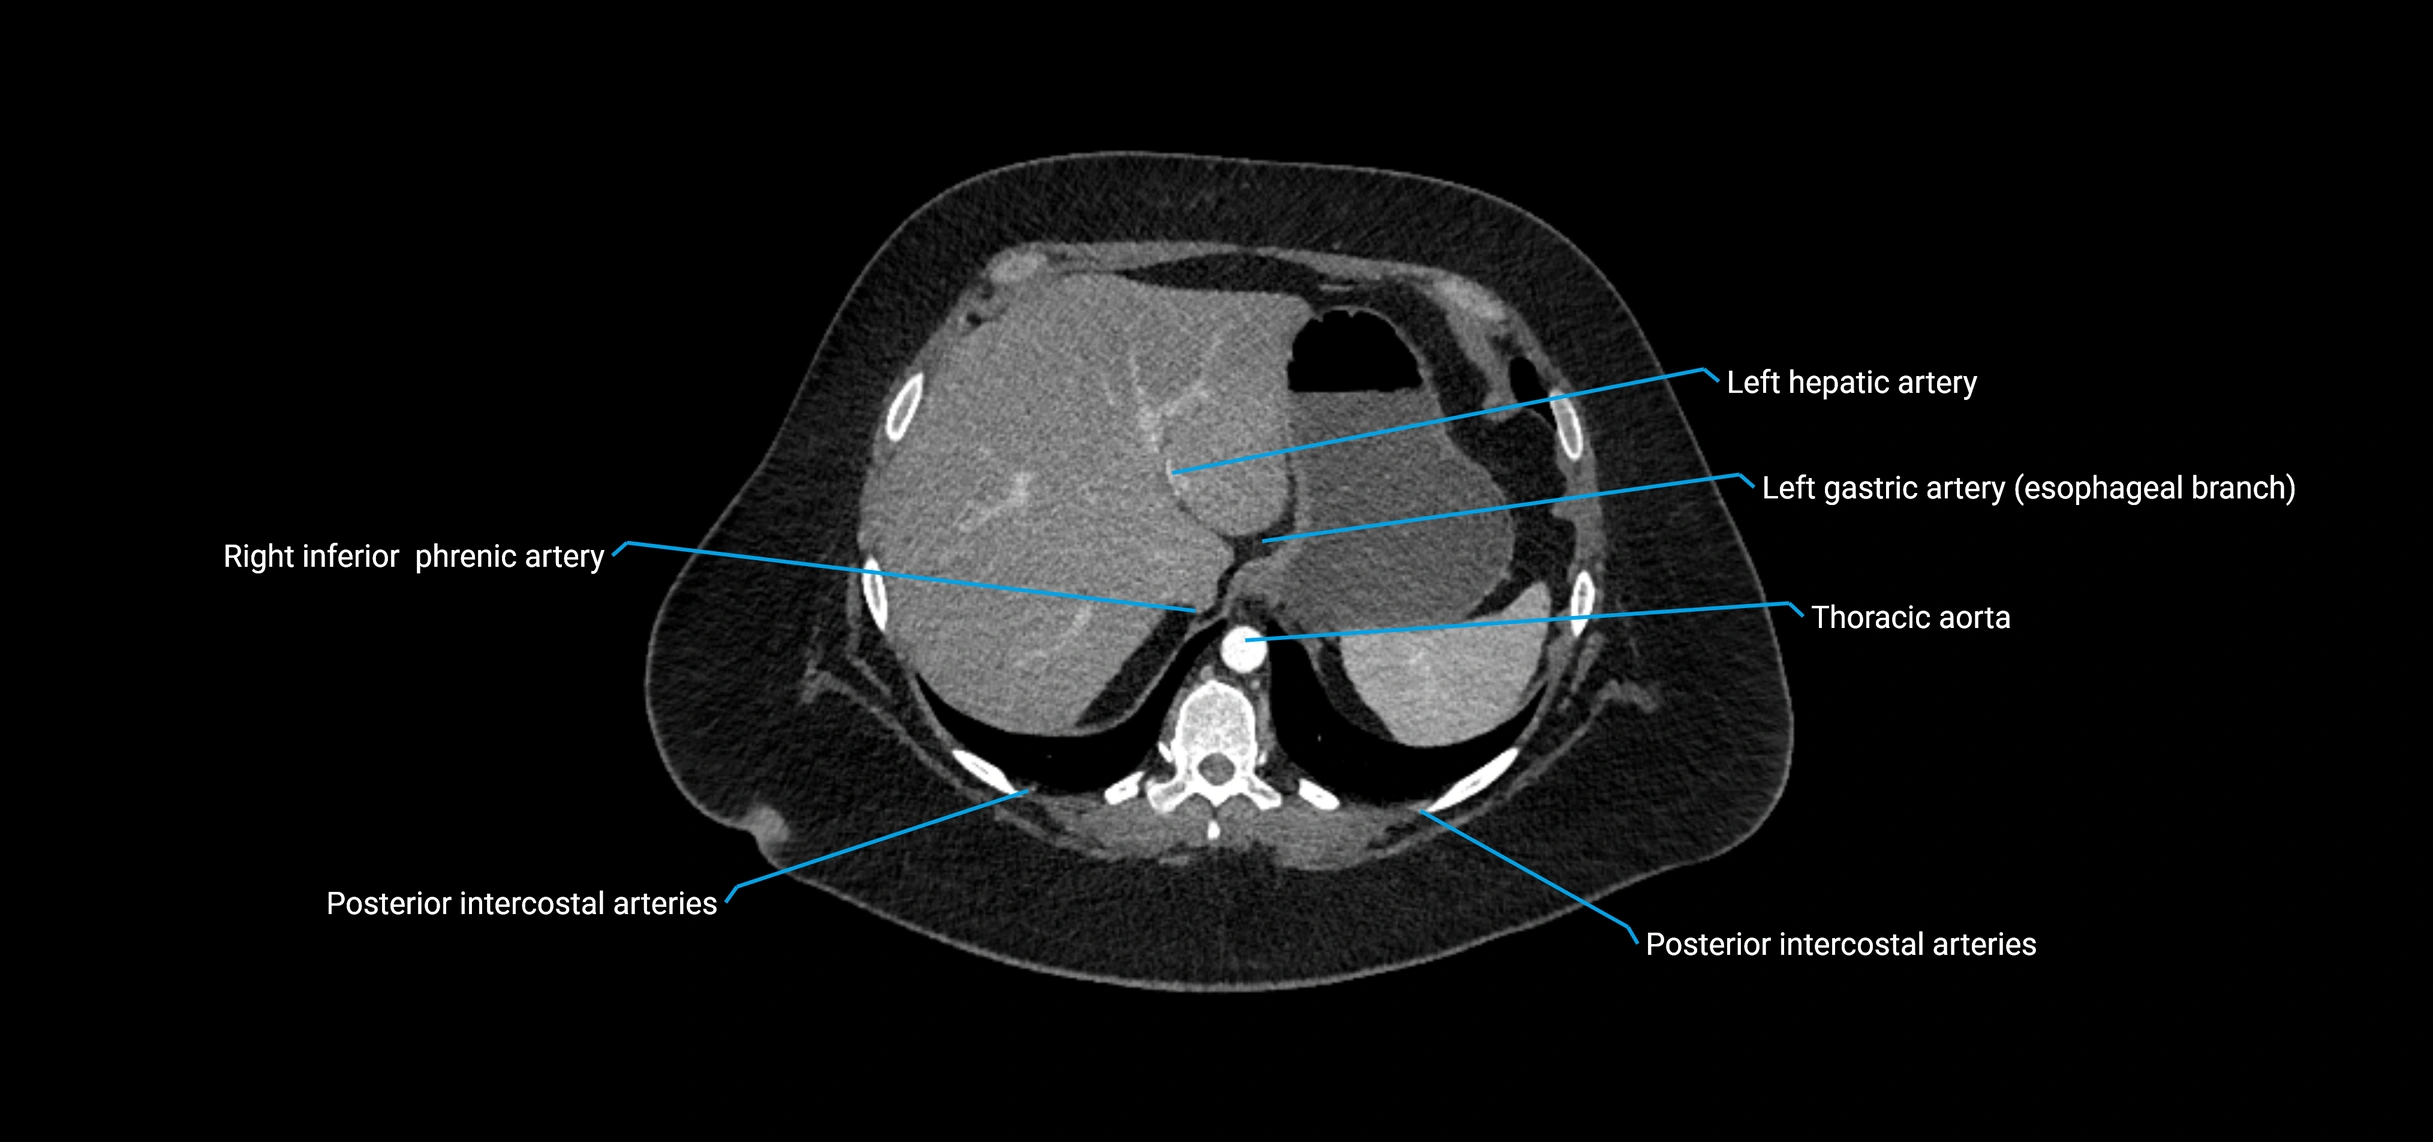

CT images

image

Contrast-enhanced CT (CTA):

• Gold standard for abdominal aortic imaging

• Provides excellent detail of lumen, wall, aneurysm, thrombus, and branch vessels

• Multiplanar and 3D reconstructions help in aneurysm measurement, stent graft planning, and dissection evaluation